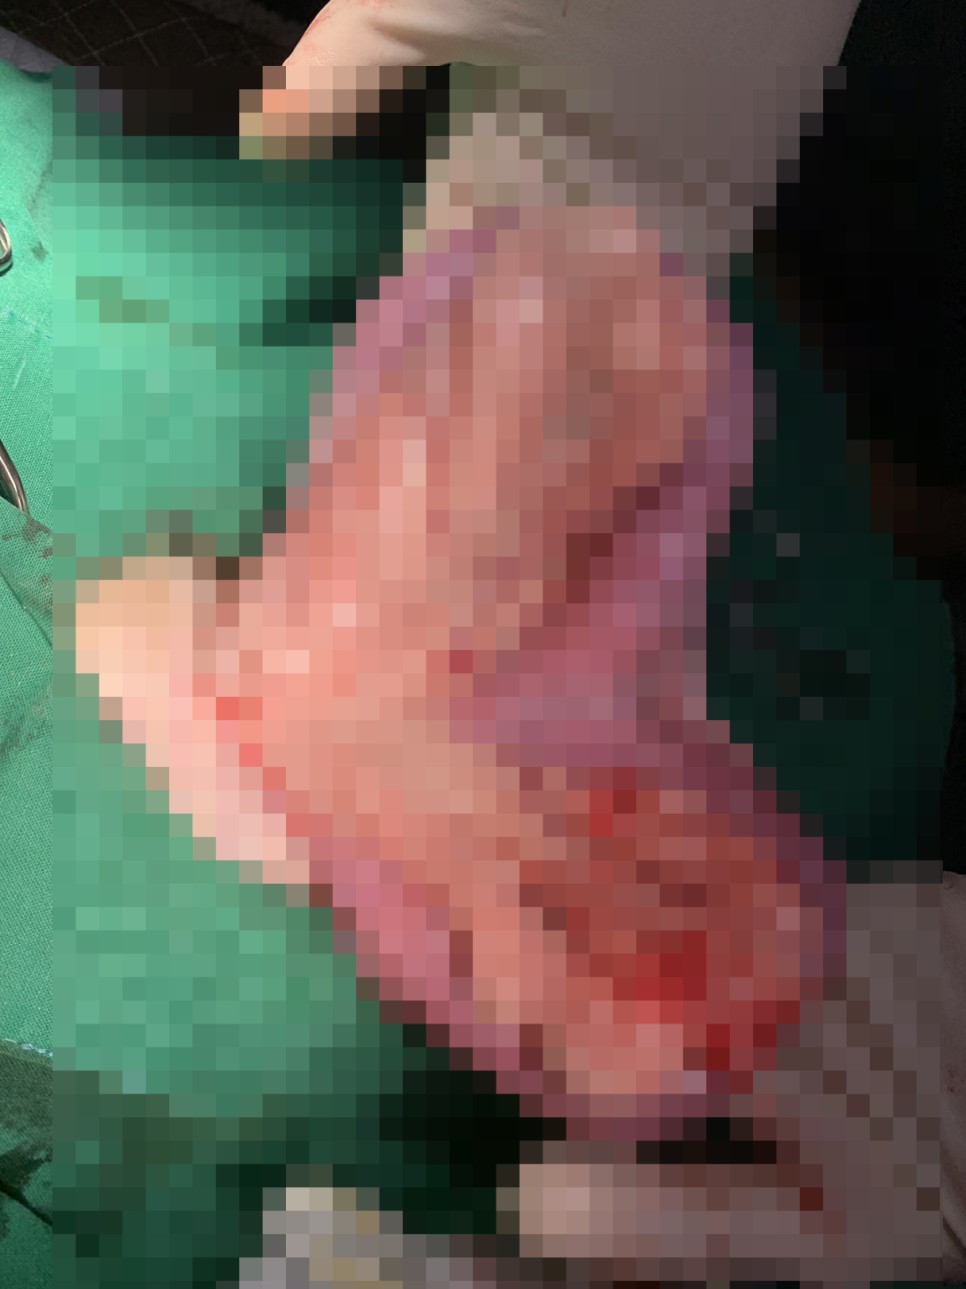

치료, 시술 대형견에 대한 수술은 안전한 마취와 수술 진행을 위해 전문적인 장비, 스텝, 수의사가 필요합니다.

안전하고 신속하게 수술을 잘 마쳤습니다.

곪아 있는 거대한 자궁과 난소를 제거했어요.